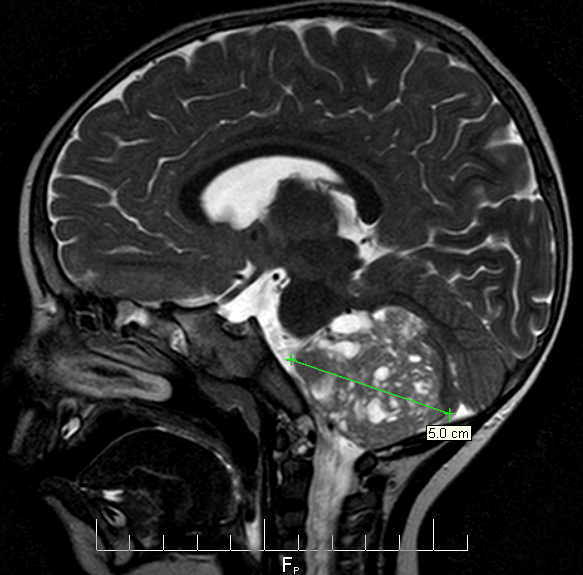

At Sick Kids we were seen by Dr. Audrey Segal who was the first person to truly listen to our story and patiently note all the details, and she ordered some bloodwork and a CT scan. By around 10:30pm, Audrey had to break the devastating news that Gavin had a large posterior fossa brain tumour.

MRI

About 3 weeks later we received the final diagnosis from the pathology team: Cribriform Neuroepithelial Tumor (CRINET) which is a variant of Atypical Teratoid Rhabdoid Tumor (AT/RT). AT/RT is a rare, aggressive cancer with a low survival rate, but CRINET has a slightly better prognosis. CRINET has only recently been identified so the case history (only 2 children at the time) makes it difficult to know how Gavin will fare. The other two children are long-term survivors, but were initially misdiagnosed and treated with protocols designed for other tumour types.